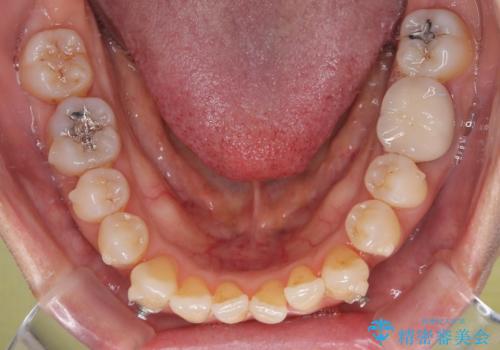

受け口と八重歯を改善 インビザライン矯正治療

受け口傾向のインビザライン矯正は比較的治療を行いやすいため、きれいに仕上げることができました。舌の突出癖が顕著であったため、改善のためのトレーニングをしっかりと行っていただきました。